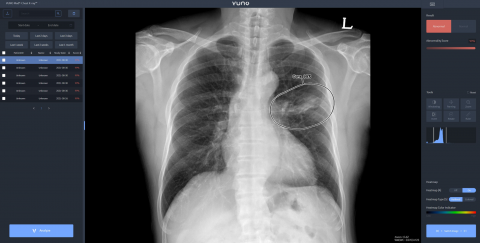

의료 인공지능(AI) 기업 뷰노는 아랍에미리트(UAE) 국군 병원인 자이드 군 병원(Zayed Military Hospital)에 인공지능 기반 엑스레이(X-ray) 판독 보조 솔루션을 공급했다고 22일 밝혔다. 자이드 군 병원에 도입된 솔루션은 이동형 엑스레이 장비에 뷰노의 AI 기반 흉부 엑스레이 판독 보조 솔루션 뷰노메드 체스트 엑스레이™(VUNO Med®-Chest X-ray™)를 탑재한 패키지 제품이다. 별도의 차폐 시설 없이 다양한 상황에서도 쉽게 환자의 흉부 엑스